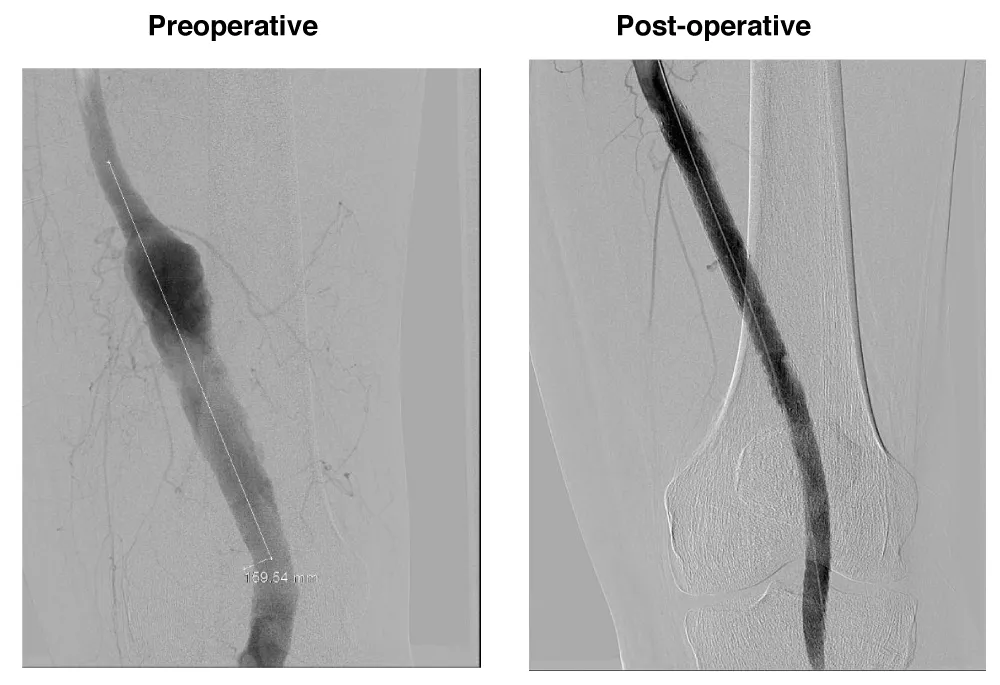

A male patient, 63 years, with arterial hypertension and dyslipidemia, was admitted with an asymptomatic popliteal artery aneurysm in the left Lower limb measuring 3,1 cm, discovered after an acute arterial occlusion at the right Lower limb due to popliteal artery aneurysm thrombosis. The following measures were observed: proximal neck diameter 10,21 mm, distal neck diameter 9,98 mm, with a diameter of 56 mm and 250 mm aneurysm length. The patient underwent endovascular treatment with the popliteal implant of endoprosthesis Wrapsody® 12x80 mm at the distal neck, followed by the implant of Wrapsody 12x125 mm and Wrapsody 12x80 mm at the proximal neck, followed by catheter balloon dilatation. The final image showed excellent results with no endoleaks (Figure 1). The patient was discharged from the hospital on the on the first postoperative day with Rivaroxaban 20 mg/day and a 6-month follow-up showed endoprosthesis patency with excellent flow and run-off.

Figure 1: Endovascular repair of a 63-year-old male with left popliteal artery aneurysm (56 mm): Preoperative imaging shows fusiform dilation of the popliteal artery. Postoperative image demonstrates successful deployment of three Wrapsody® endoprostheses (12×80 mm, 12×125 mm, and 12×80 mm) with complete exclusion of the aneurysm and no evidence of endoleak.